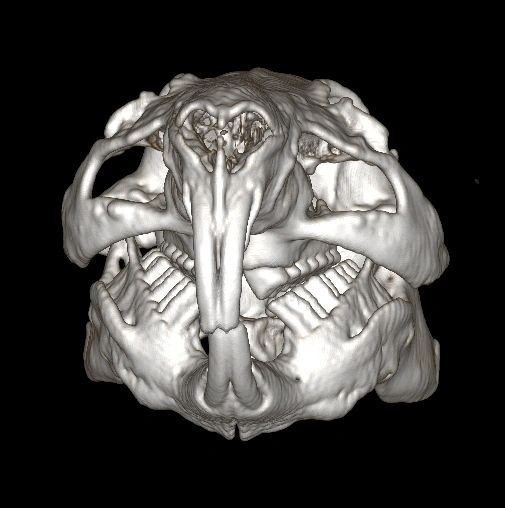

Guinea pig skull clearance

Guinea pig skull clearance

Skull Store These are real guinea pig Cavia porcellus

Guinea pig dentition

Skull of a guinea pig Cavia porcellus isolated in black. Front